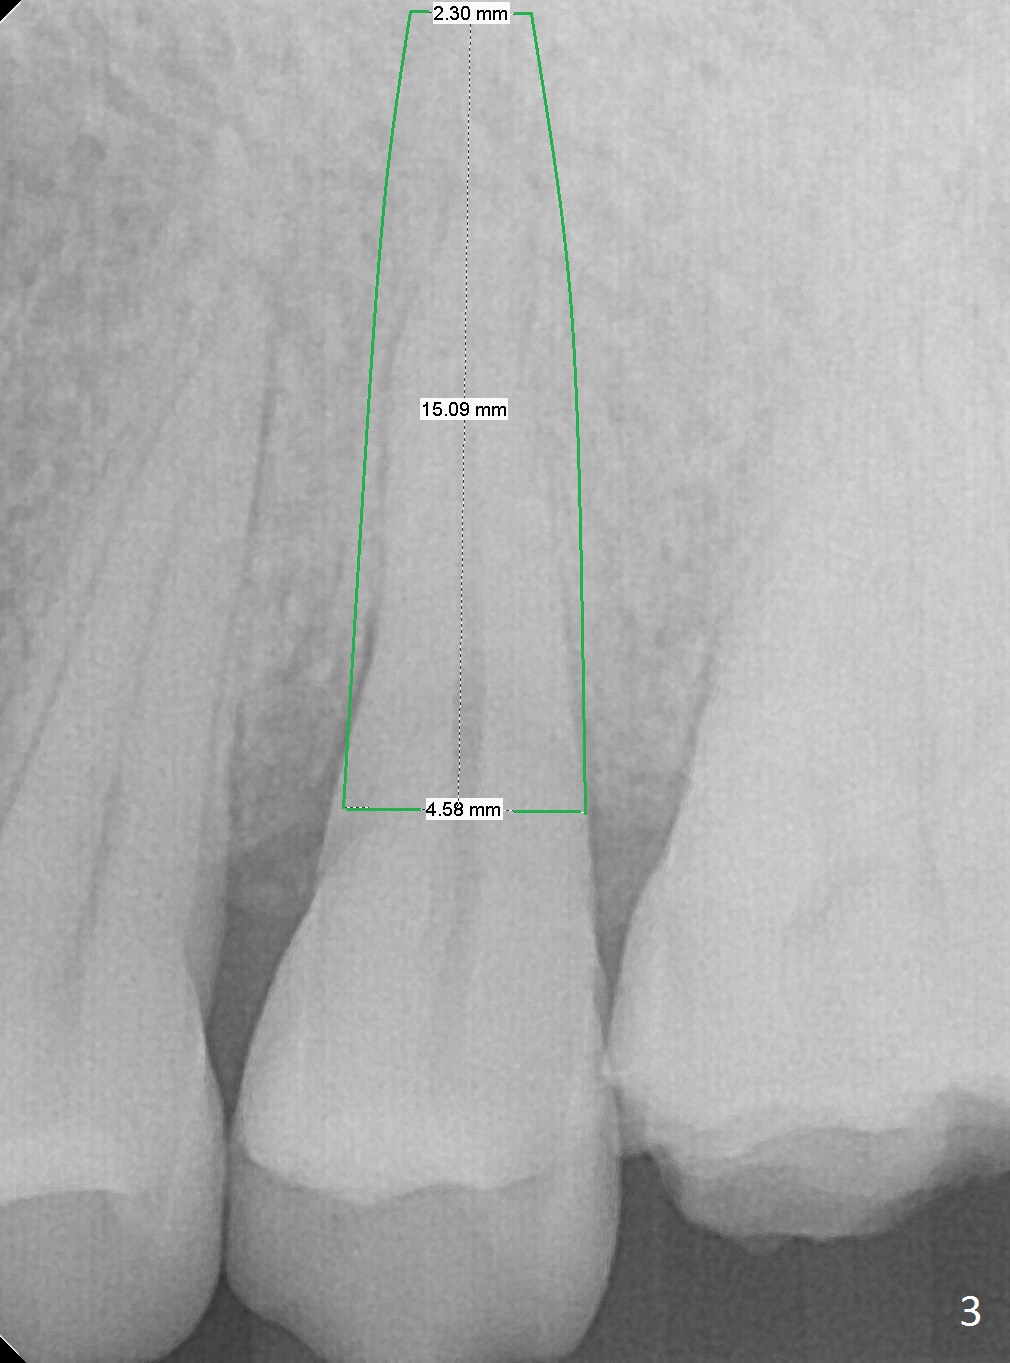

A 42-year-old woman presents to clinic with cc "top left tooth cracks upon biting on a small piece of stone". The buccal gingiva is tender, corresponding to the loose buccal segment of the tooth #13 (Fig.1). The crack may be secondary to severe wear of the 1st molar (Fig.1,2) in addition to deep slope of the affected tooth. A 4.5x15 mm IBS implant will be placed (Fig.3). Take PA following pilot drilling.